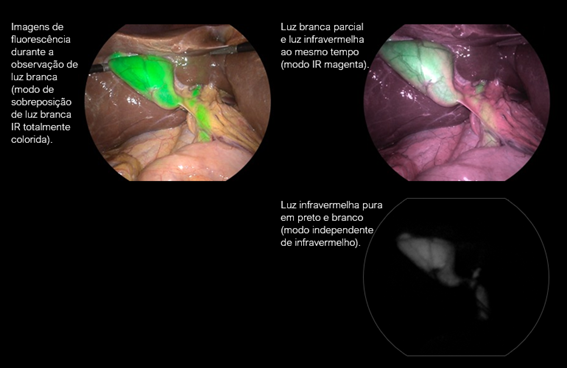

O sistema de videocirurgia VISERA ELITE™ III da Olympus oferece visualização em infravermelho com alta definição e contraste. Equipado com modos monocromático e de sobreposição (imagem colorida + fluorescência), ele potencializa a segurança cirúrgica em procedimentos minimamente invasivos.